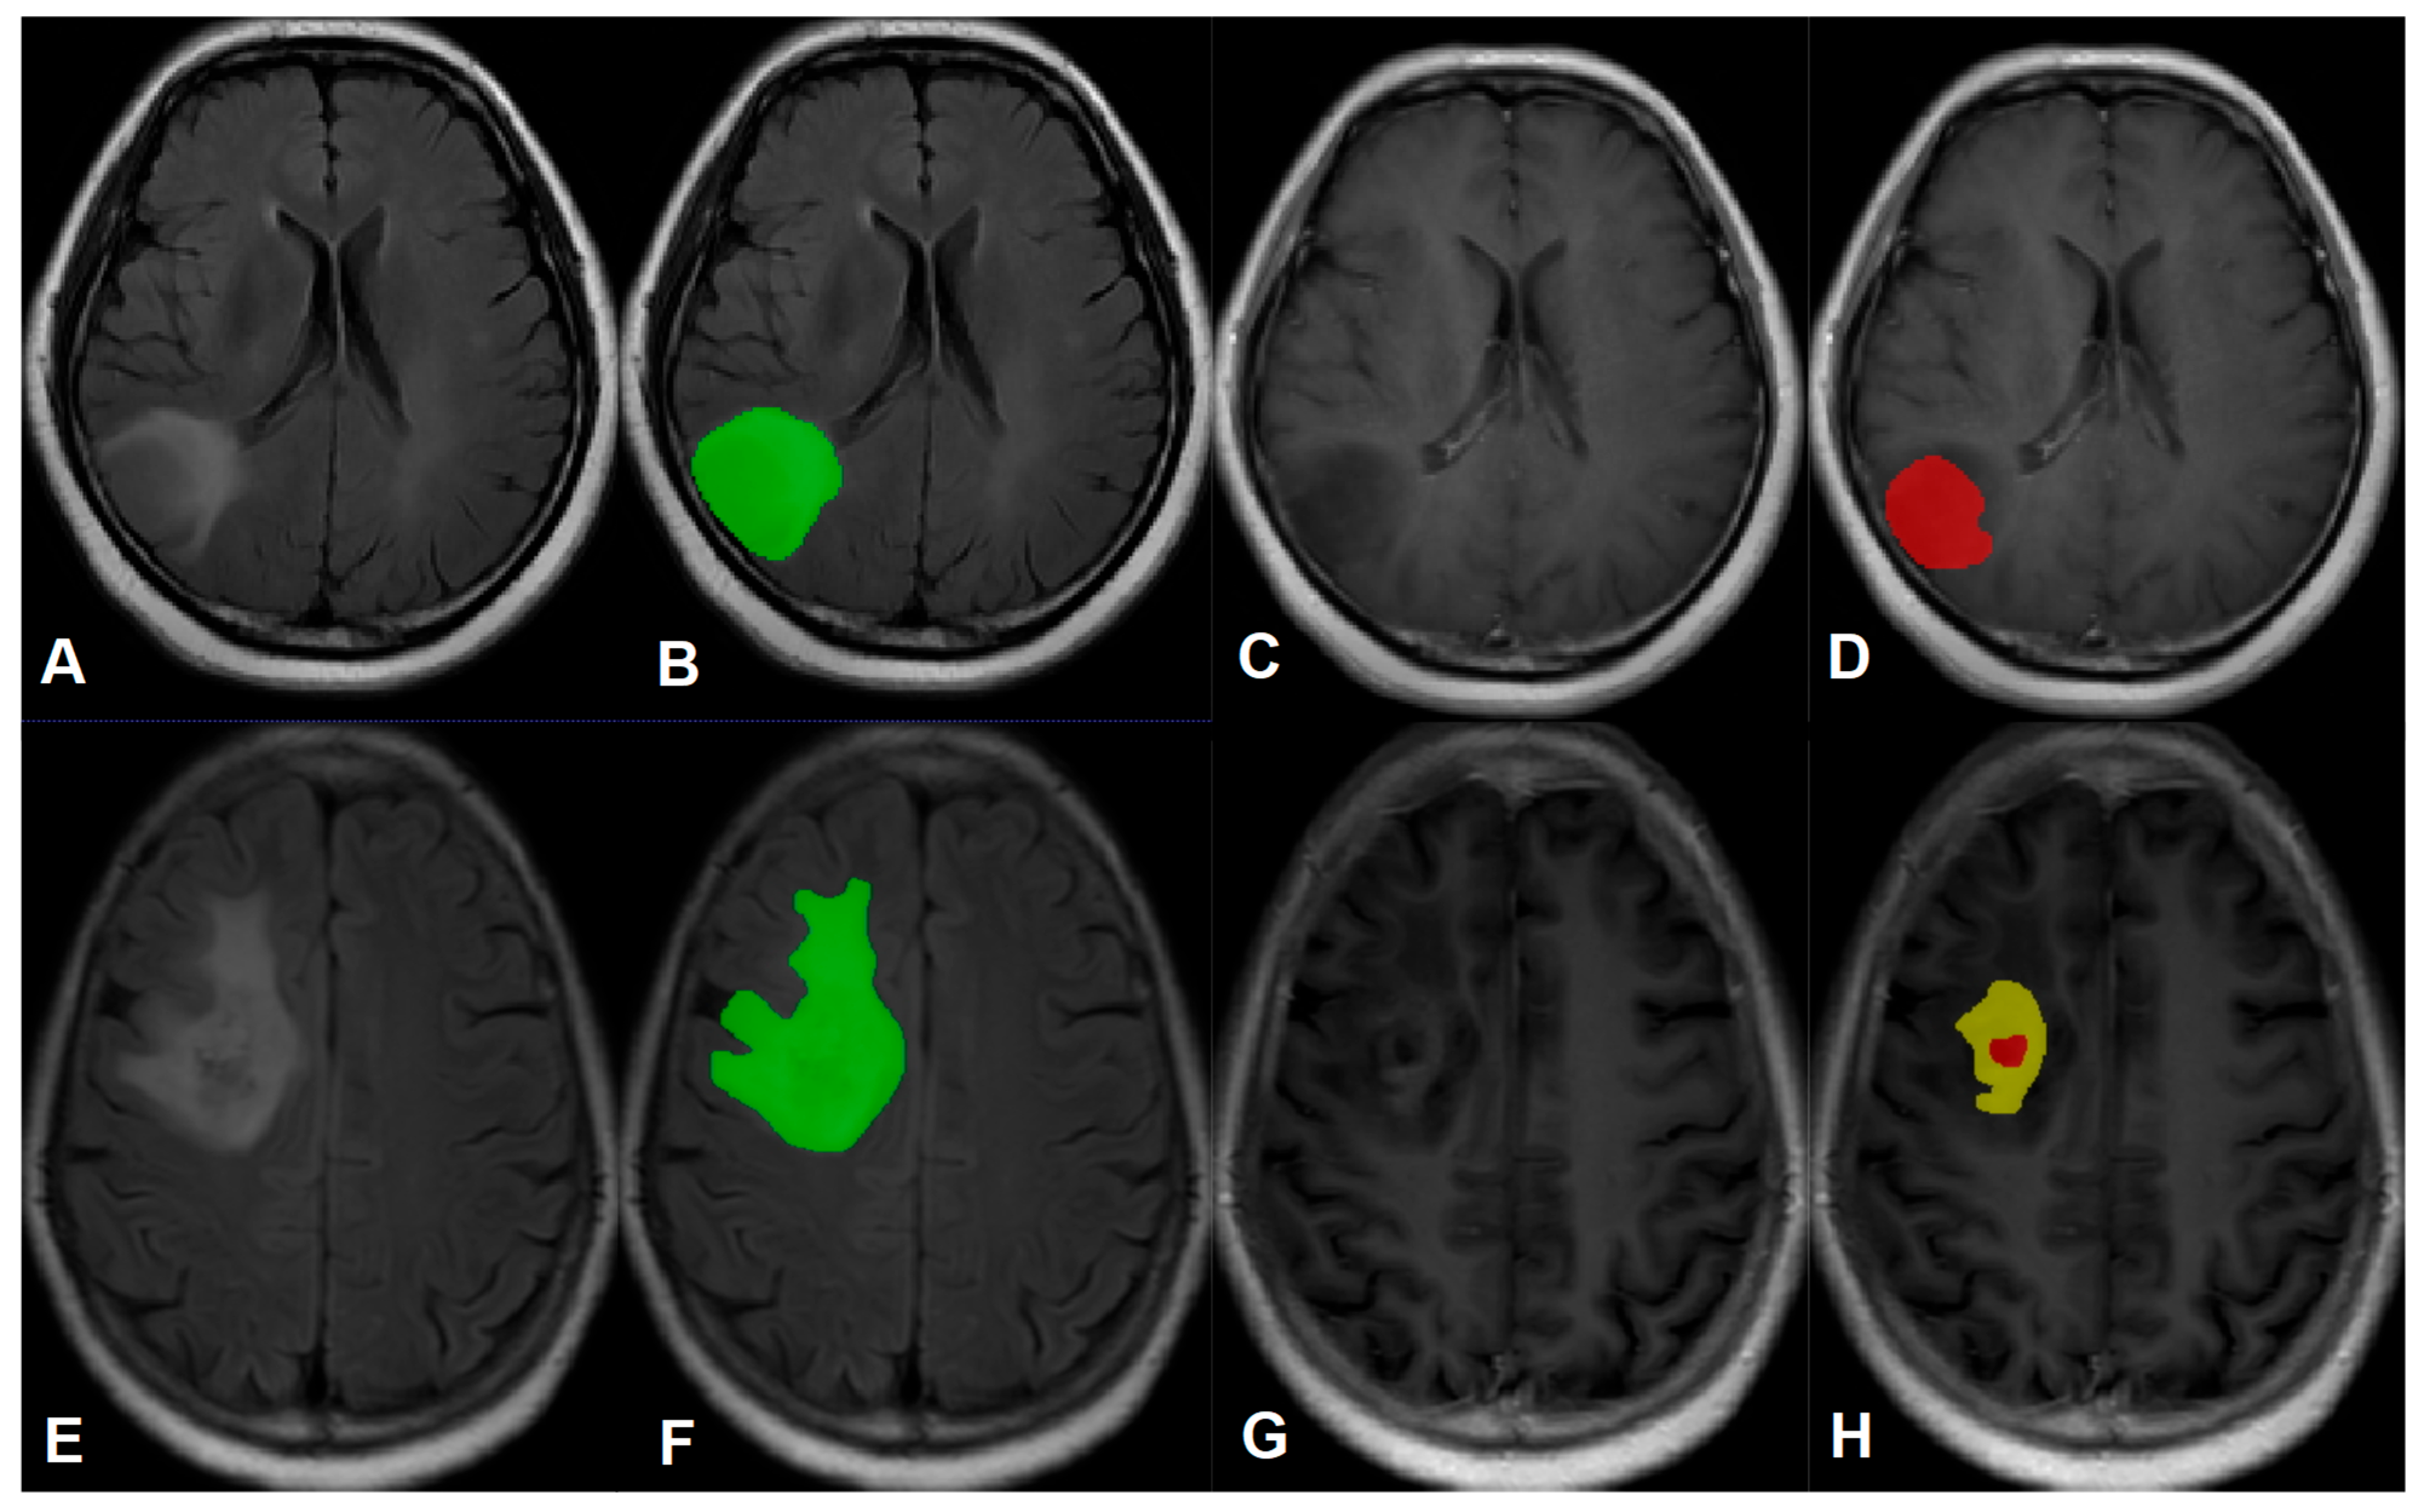

2.1. Patients

6. Image Segmentation